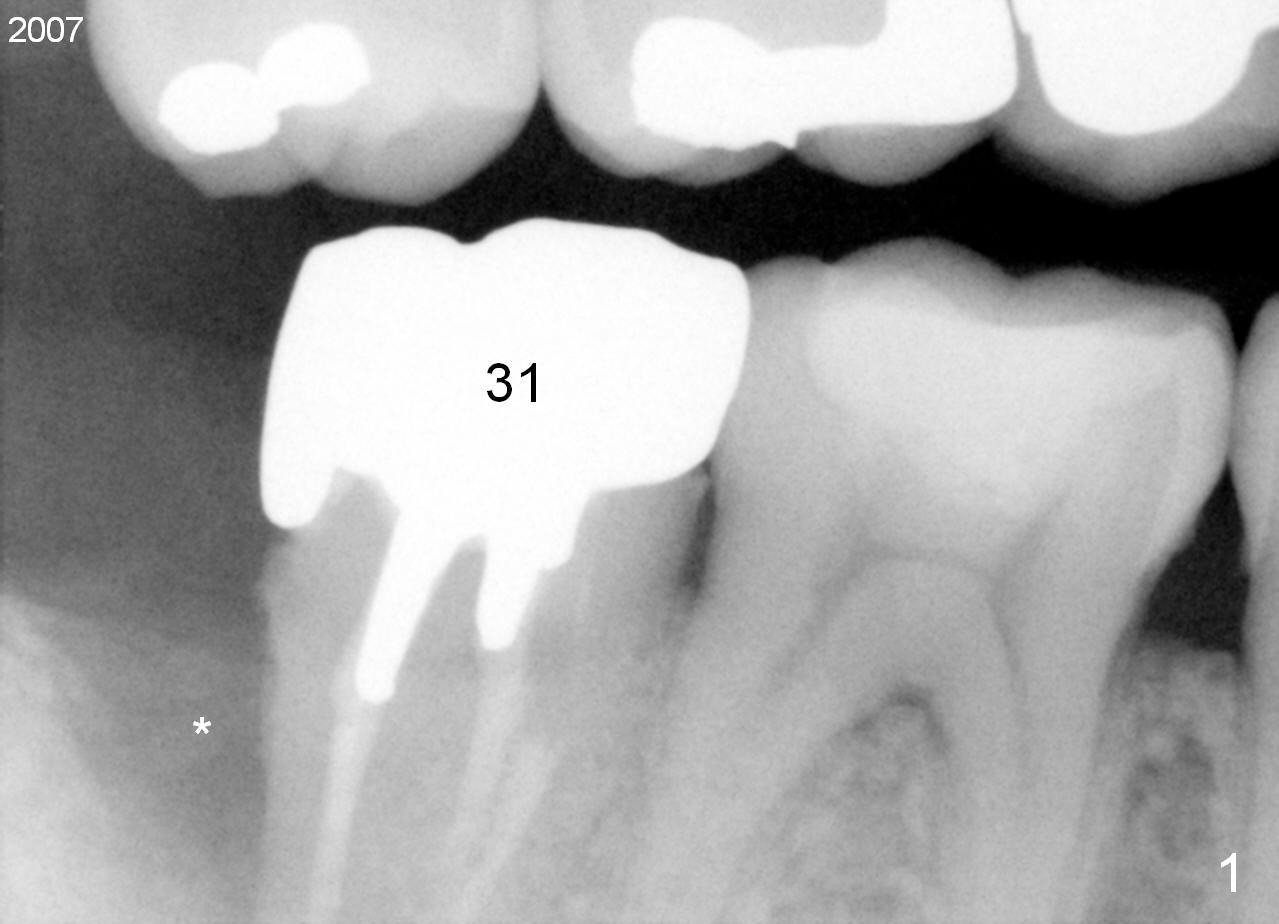

A 44-year-old man has had an asymptomatic distal defect of the tooth #31 for 8 years (Fig.1-5). Recently there is an acute episode of swelling and pain. A fistula develops mesiobucally. Panoramic X-ray films tend to show that the distal defect is deep (Fig.2,5; yellow dashed line: upper border of the Inferior Alveolar Canal). In addition, the distal defect may be not even buccolingually, as indicated by white and red arrowheads in Fig.3,4. Following placement of a 6.9x10 mm bone-level implant, a 7.8x4 (4.5) mm cemented abutment is inserted for try in (Fig.6). When it is fit, it is removed and a cover screw is temporarily placed. A piece of Osteotape (~10x4 mm) is placed distobuccally or distolingually (depending upon which wall is lower). A small amount of bone graft is packed between the most coronal portion of the implant and the Osteotape. The cover screw is then removed and the abutment is re-inserted and tightened by hand. An immediate provisional is fabricated with well-trimmed margin. Reline is done if necessary for securely holding bone graft in place. A new PA is to be taken prior to surgery to determine the extent of the lesion. Photos are taken to show the mesiobuccal fistula. Return to Lower Molar Immediate Implant Xin Wei, DDS, PhD, MS 1st edition 04/12/2015, last revision 05/25/2018